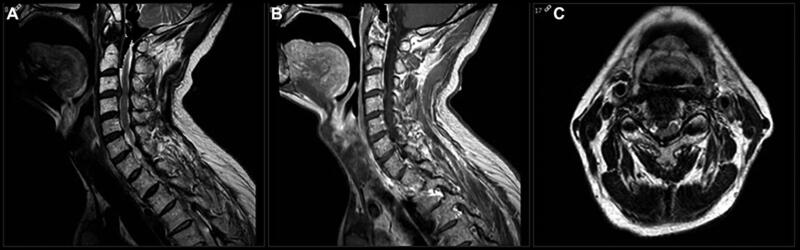

Bệnh nhân nam, 60 tuổi đi khám vì đau cổ tiến triển từ vài tháng nay, tê rần cánh tay phải, và bàn tay phải trở nên vụng về. Ông cho biết ngày càng mất thăng bằng trong đi lại, mặc dù vẫn còn khả năng làm công việc của một người quản gia. Dấu hiệu sinh tồn không có gì đặc biệt. Các xét nghiệm máu thường quy bình thường. MRI chụp có kết quả như hình 3.

Đường mổ phía trước bao gồm lấy bỏ đĩa đệm và làm cứng cột sống (Anterior Cervical Discectomy and Fusion-ACDF) (hình 3), có thể kết hợp thêm cắt bỏ đốt sống. Lợi ích của ACDF là giải quyết nguyên nhân trực tiếp gây chèn ép tủy sống như gai xương hoặc lồi đĩa đệm. Hơn nữa, giải ép gián tiếp lổ liên hợp có thể đạt được bằng cách đặt miếng ghép đĩa đệm, việc này cũng giúp phục hồi lại chiều cao đĩa đệm và độ ưỡn (lordosis) của cột sống ở tầng đó. Tuy nhiên, nếu bệnh lý nằm phía sau của đốt sống (ví đụ: phì đại dây chằng dọc sau), cắt bỏ thân sống sẽ giúp giải ép tủy sống an toàn hơn. Biến chứng phổ biến nhất của ACDF là khó nuốt và khó phát âm. Tổn thương dây thần kinh thanh quản quặt ngược trong quá trình phẫu thuật có thể gây liệt dây thanh âm. Biến chứng ít gặp hơn là tổn thương động mạch đốt sống trong khi giải ép lổ liên hợp, tổn thương thực quản trong quá trình vén và đặt phương tiện, và tụ máu sau mổ gây suy hô hấp.

Hình 3. Xquang phim sau mổ ACDF C3-C4

- B. BN bị bệnh lý tủy cổ do thoái hóa cột sống cổ. MRI cho thấy khối thoát vị lớn, bên phải ở đĩa đệm C3-C4 gây hẹp ống sống dữ dội, tình trạng này làm nặng thêm tình trạng hẹp ống sống cổ bẩm sinh của BN (<13mm). Ở các tầng khác của cột sống cổ, các đĩa đệm lồi ít hơn và có tình trạng phì đại dây chằng, gây ra hẹp ống sống vừa phải. MRI có tiêm Gadolinium không có hình ảnh bắt thuốc cản quang của những thương tổn trong bệnh lý di căn, nhiễm trùng hoặc rối loạn thoái hóa myelin.

- B. Trong bối cảnh BN có dấu hiệu bệnh lý tủy rõ, phẫu thuật nên được chỉ định để ngăn chặn tình trạng tổn thương tủy tiến triển nặng hơn. Điều trị bảo tồn bằng thuốc không thể làm dừng lại được tình trạng thoái hóa. Bệnh nhân bị thoát vị đĩa đệm cổ C3-C4 rõ rệt, nên chỉ định tiến hành ACDF ở tầng này là phù hợp.